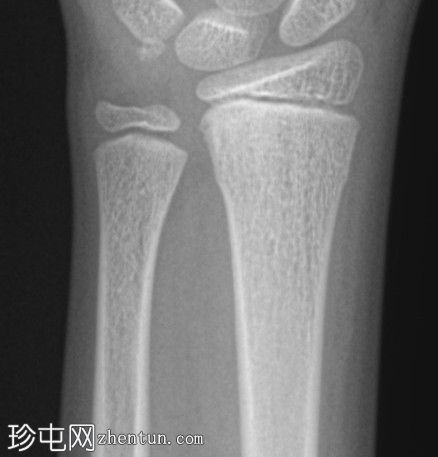

正位片

桡骨远端干骺端皮质骨隆起,符合骨性骨折(Cuckle fracture)的特征。

骨性骨折(Cuckle fracture)是指长骨干的不完全性骨折,其特征是皮质骨隆起;常见于儿童,常累及桡骨远端干骺端。